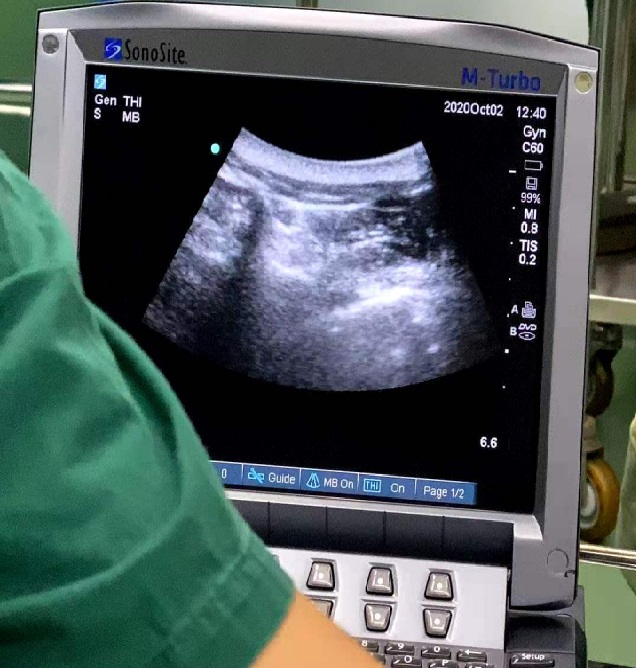

超声是疼痛医师另一双“眼睛”,通过超声定位可以更加准确找到神经来治疗各类神经病理性疼痛,这是椎旁神经阻滞治疗肋间神经痛。